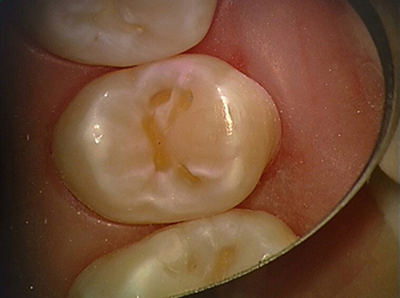

Erweiterte Fissurenversiegelung und Mikrofüllung

4